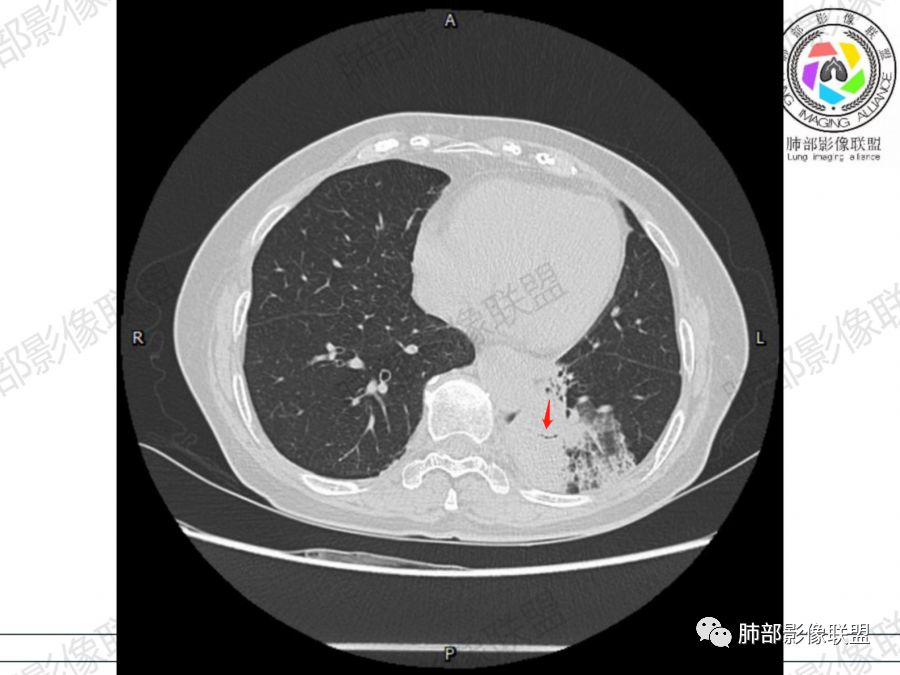

晨读病例,老年人男性 左肺下叶病灶,实性病变加上边界清晰的磨玻璃影,实性病变可见明显的膨胀性生长,增强实性部分可见血管照影征,考虑腺癌,粘液腺癌可能。

左肺下叶胸膜下混合磨玻璃影,磨玻璃边界清晰,支气管进入后堵塞,增强轻中度强化,无明显坏死空洞。

空腔+铺路石征+边界清楚GGO+病灶内血管局部扭曲+强化不均匀+病史长,指向腺癌,特别是粘液腺癌

晨读:左肺下叶胸膜下实性高密度影,部分伴有网格样增厚,内部可见小空泡,壁光滑,周围伴有磨玻璃影,边界清,近端可见支气管穿行,远端支气管堵塞,胸膜下脂肪间隙可见,病变整体收缩,部分有彭隆,增强后可见血管穿行,强化尚均匀。

左肺下叶实变及磨玻璃影,宽基底与胸膜相远,磨玻璃边界清晰,边缘膨隆,病变内近端支气管堵塞,不均匀强化,可见血管影,考虑腺癌,鉴别结核

胸CT:左下叶胸膜下大片斑片影,长轴沿胸膜分布,实变、GGO混杂,磨玻璃边界清晰,粘液密度,小叶内间隔增厚,支气管进入后堵塞(枯枝),增强轻中度强化,血管造影征。常规考虑:肺腺癌?淋巴瘤?鉴别不典型病原体感染。

周围GGO,呈碎石路征,边界清楚

主体病灶

2、影像表现:无肺气肿背景,病变定位于左肺下叶背内侧基底段,病灶呈不规则团块影,靠近胸膜侧,其内密度不均匀,内见空洞、实变及磨玻璃影,磨玻璃影呈碎石路征,边界清楚,实性肿块边界膨隆,其内见空洞。空洞周围比较实。病灶较大的支气管通畅,细小的支气管成“枯枝征”。无胸膜增厚及胸膜腔积液,增强扫描呈中度强化,见血管造影征。